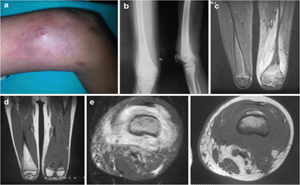

PubMed Central: Published on 2020 August

AHOM was defined as any bone

infection with a period between symptoms onset and diagnosis < two weeks.

AHOM was defined complicated in the

presence of sepsis, septic shock, arthritis, cellulitis, sub-periosteal or

muscle abscess, deep vein thrombosis pathological fracture, septic emboli or

hosp...